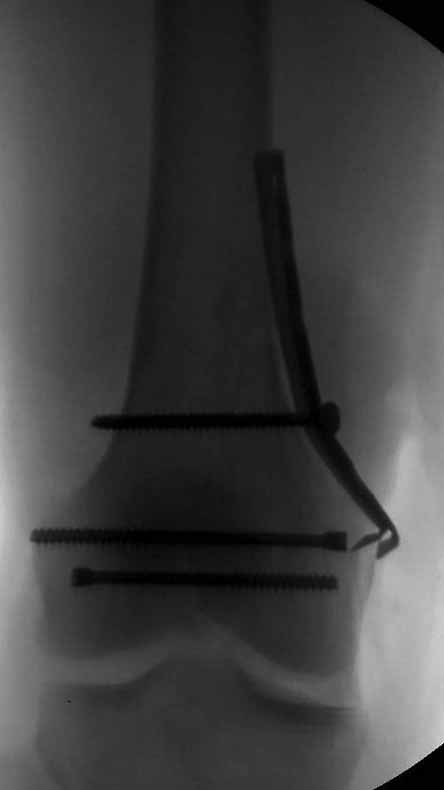

Здесь пример медиальной пластины и латеральный комбинированный метод (у второго больного старый перелом тибиал плато, леченный где то и когда то)

наружный мыщелок не дорепонироавн - это приводит к вальгусной деформации оси коленного сустава, очень критично для последующей функции.